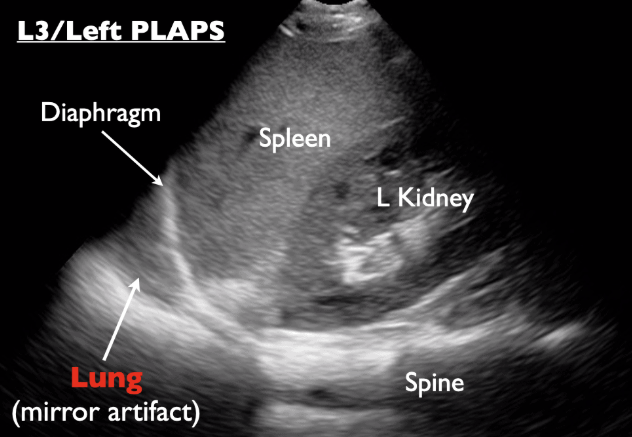

ULTRASOUND PLEURAL SPACE